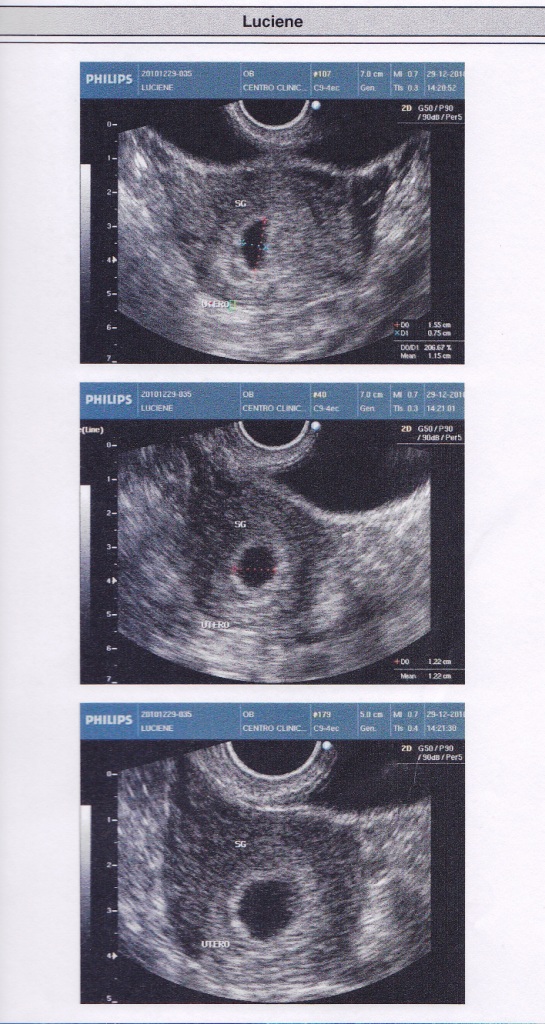

Um ultrassom de 6 semanas nos mostrou o quanto o nosso bebê está se desenvolvendo. Foi incrível poder ver o coraçãozinho batendo, mesmo que ainda pequenino, já é uma prova do milagre da vida acontecendo dentro de mim.

Ultrassom de 6 semanasEstamos maravilhados com a imagem do ultrassom, tão nítida e emocionante. É uma experiência que nos enche de amor e gratidão por essa vida que está se formando em meu ventre.

Vlog: Ultrassom de 6 semanas | Diário do bebê | Grávida aos 17E para tornar esse diário ainda mais especial, vamos fazer vídeos toda semana para mostrarmos aos nossos amigos e familiares como nosso bebê está crescendo e se desenvolvendo. No último vídeo, compartilhamos o momento emocionante do ultrassom de 6 semanas. A imagem é simplesmente linda!